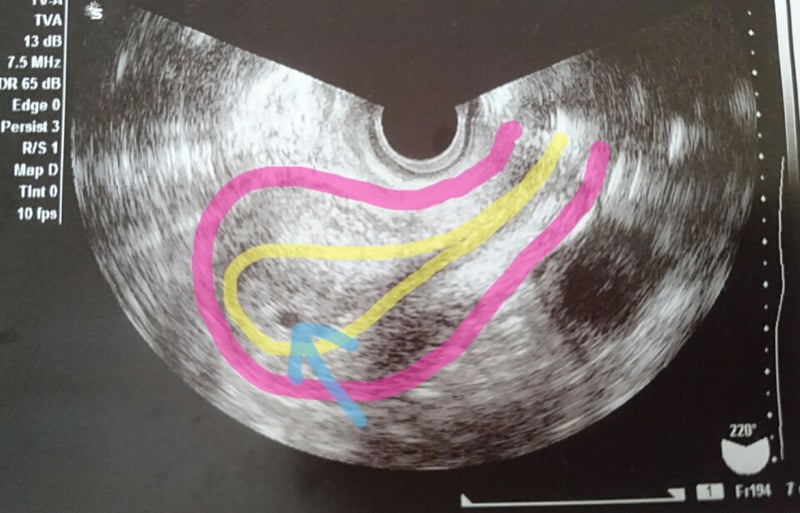

孕婦懷有雙胞胎 4個症狀很明顯 符合3條以上 恭喜你好孕雙胞胎 每日頭條

6週照到雙胚囊 但胚囊只有5週大 還沒有囊黃 胚胎 及心跳 Babyhome親子討論區